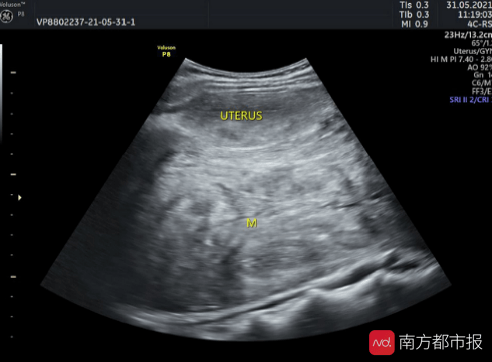

“未见其人 , 先见其腹”!体重50公斤的黄女士来暨南大学附属第一医院就诊时 , 她的肚子却巨大得异常突兀 , 经过全腹CT检查 , 结果显示:腹盆腔内见一巨大软组织肿块影 , 大小约22cm*10cm*28cm 。 子宫后发盆腹腔探及一实性光团 , 考虑盆腹腔巨大实性占位病变 。 抽血检查显示 , 包括肿瘤标记物均正常 。

术前CT检查 腹腔内巨大肿物